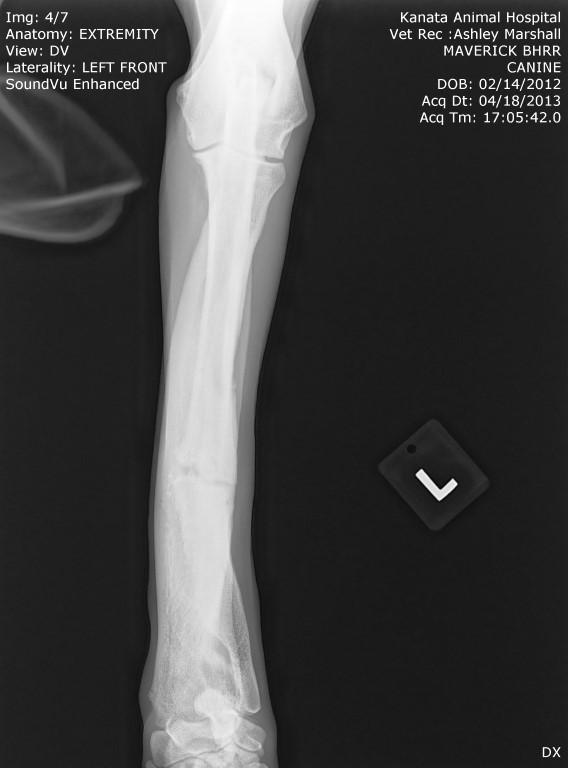

His surgery to remove the implant on his left front leg after a sudden rejection/infection with the plate screws was on September 24th. This is his fourth leg surgery. He had two surgeries on his front legs which were deformed when he first arrived to BHRR and then now he has had to have two more surgeries due to reacting to the Implants.

Surgery started late yet all is done and The Mavie, our true Iron Man has his ‘new’ leg!

BHRR’s Mavie is having that front left leg implant removed. He developed a sudden infection and rejection of the plate/screws.

It does appear that I may well be correct that after 2 years and four months plus from first having the original leg surgery, he is now rejecting this implant. He had this leg first operated on in July 2013. frown emoticon

BHRR’s Mavie, for those who are not familiar with his journey has had two surgeries on his front legs, ended up reacting to the fixator on the left front leg, then last November rejected the implant in the right front leg and now, is having symptoms very similar on the left front leg.

Sadly, BHRR’s Maverick began to suddenly favour the left front leg that has the remaining implant in it last night. As of this AM, he was not weight bearing and though he did not have a fever, it was a bit warm and swollen and he was brought into KAH.

As many are aware, in November of 2014, BHRR’s Maverick, had a violent aggressive reaction to the implant in his right front leg and had to spend several months on strong antibiotics, had to have an emergency surgery to remove the plate/screws and was treated for a terrible abscess from reacting to the implant. His ortho specialist even cultured the implant to see what may be brewing on it…..

How it started with his right leg is how his left leg is now ‘appearing’ to be.

Needless to say, I was and am worried and a thorough exam was done, x-rays under sedation – HENCE, this lovely snoring sleepy photo of BHRR’s Mavie on the x-ray table!

At this time the integrity of the plate and leg look good, he is stil not running a fever and he will be on Tramadol and Deramaxx for pain and inflammation.